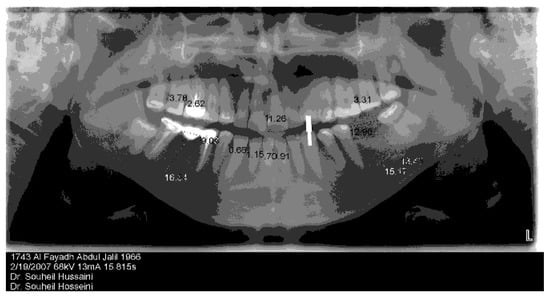

- Pre-operative CBCT prioritizing Screw Retained Prosthesis.